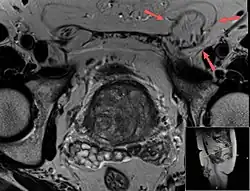

Ultrasound of an indirect hernia containing fat, with testicle seen at right.

T2 weighted MRI of the same case (done for another purpose), also demonstrating fat content.

When assessed by ultrasound or cross sectional imaging with CT or MRI, the major differential in diagnosing indirect inguinal hernias is differentiation from spermatic cord lipomas, as both can contain only fat and extend along the inguinal canal into the scrotum.[22]

On axial CT, lipomas originate inferior or lateral to the cord, and are located inside the cremaster muscle, while inguinal hernias lie anteromedial to the cord and are not intramuscular. Large lipomas may appear nearly indistinguishable as the fat engulfs anatomic boundaries, but they do not change position with coughing or straining.[22]